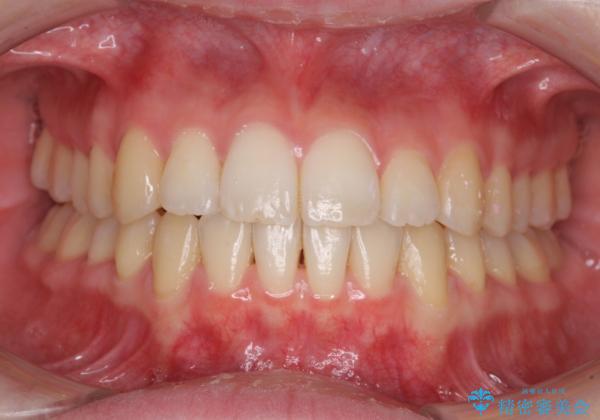

気になる前歯を整えたい インビザライン・ライトでの矯正治療

- ちょっとしたデコボコを整えたいとのことで来院された患者様です。

歯列不正は軽微であったため、インビザライン・ライトにより、費用を抑えて矯正治療を行うこととしました。

上下前歯の捻れが改善され、患者様には大変満足していただきました。